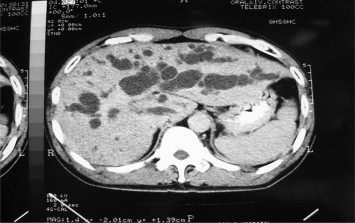

Computed tomography scan of the liver showed marked dilated bilateral ...

Figure 1.

Computed tomography scan of the liver showed marked dilated bilateral intrahepatic bile duct in type 4 hilar cholangiocarcinoma.